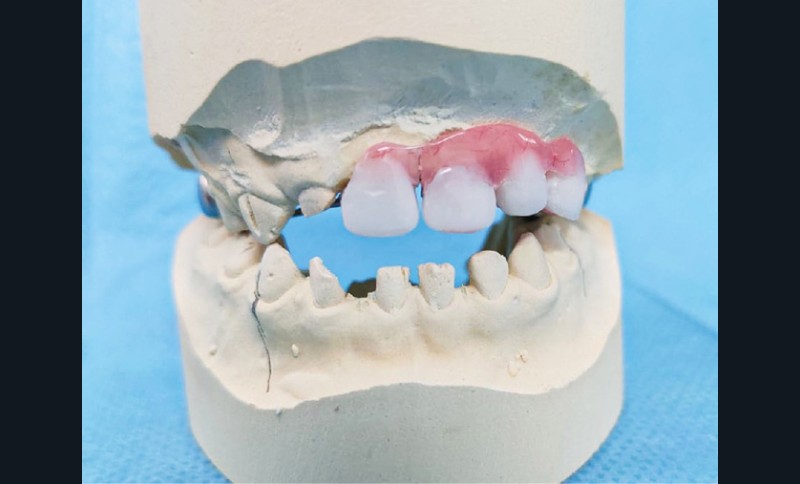

Pour les édentements limités, les dents prothétiques peuvent être fixées sur un arc palatin ou lingual, lui-même fixé sur des bagues orthodontiques ou des coiffes pédiatriques préformées (CPP) sur les secondes molaires temporaires. Ce type de mainteneurs d’espace fixe exige une hygiène buccale rigoureuse, un mauvais contrôle de plaque entraînant un risque de caries des dents porteuses des bagues ou de CPP.

Pour des édentements plus étendus, des prothèses amovibles conventionnelles, bases en résine rose avec dents prothétiques et différents types de crochets selon les cas (Adams, joncs ou encore boules), peuvent être réalisées. Pour ce type de prothèse, la coopération et le port régulier sont corrélés à une forte demande de la part des parents et de l’enfant, une hygiène rigoureuse est également indispensable.